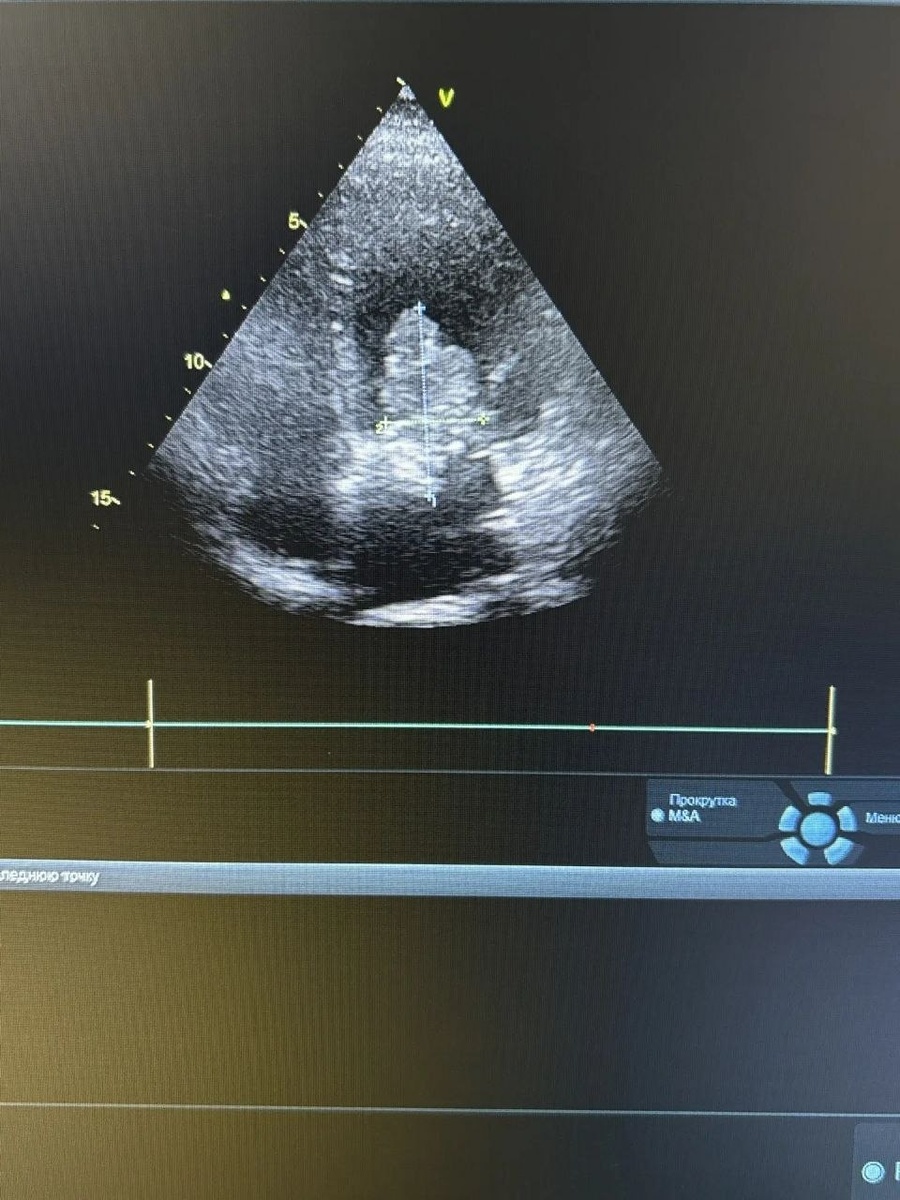

65-летняя женщина поступила в стационар Клинической больницы №2 Казани по скорой помощи. Всё началось с плановой диспансеризации: врачи заметили тревожные нарушения ритма на ЭКГ. Пациентка жаловалась на перебои в работе сердца, давящую боль за грудиной, отёки ног и даже кратковременные обмороки. Решающий момент наступил, когда врач УЗИ Регина Пилипенко обнаружила на эхокардиографии огромную доброкачественную опухоль (миксому) в левом предсердии. Она занимала почти всю его полость и могла привести к инфаркту, инсульту или внезапной смерти.

Благодаря слаженной работе врачей пациентку оперативно перевели в МКДЦ, где она готовится к хирургическому вмешательству. Эта история — яркий пример того, как вовремя пройденная диспансеризация может спасти жизнь. Желаем пациентке успешного лечения и скорейшего возвращения к привычной жизни!